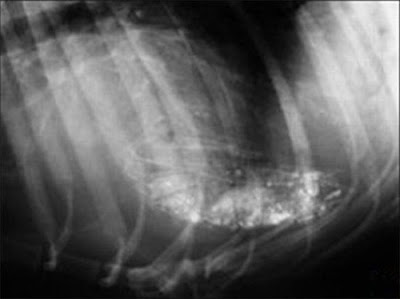

130 Nails